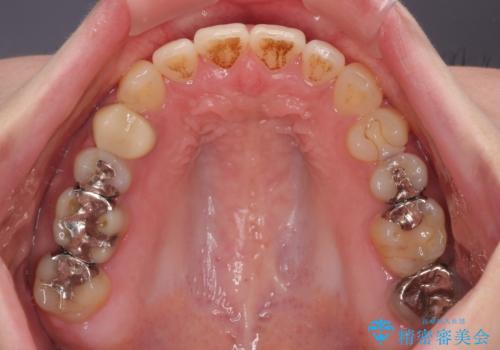

開咬をワイヤー装置で矯正治療

- 上下前歯が非接触となっている咬み合わせを気にして来院された患者様です。

開咬となっている原因の大半は、舌の突出癖によるものであるため、治療開始前から舌のトレーニングを開始し、スムーズに治療が進むようにしました。

開咬の方は、インビザライン矯正治療が適していますが、自己管理の煩わしさと、転勤の可能性がありマウスピース矯正であると通院しなくなるだろうとのことで、ワイヤー装置にて矯正治療を行うこととしました。